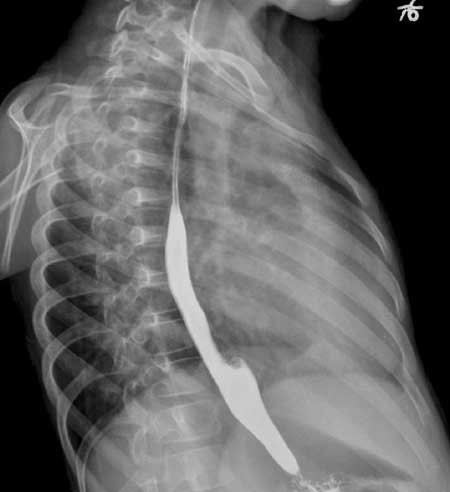

以下是引用听蝉观竹在2007-2-12 1:22:00的发言:[br]1、肺血增多-----提示有血液左向右分流;常见有房缺、室缺、动脉导管未闭。[br]2、肺动脉段突出,心尖圆隆,右前斜位肺动脉圆锥隆起------右心室增大,而左心室不增大;室缺、动脉导管未闭虽然可以右心室增大、肺动脉段突出,但同时左心室也增大,符合者就剩下房缺了。[br]3、手术前右前斜位吞钡食道压迹加深,正位片右心缘第二弓明显增大-----有心房增大。手术后右心缘第二弓正常,说明右房压力正常。[br]4、主动脉结明显缩小-----这是房缺的特征表现。[br][br]虽然没有告诉心脏杂音的性质位置,根据影像分析-------房间隔缺损。重要的一点:房缺在透视下肺门“舞蹈”明显,比其它左向右分流先心更显著。[br][br][本贴已被 听蝉观竹 于 2007-2-12 1:34:56 修改过]